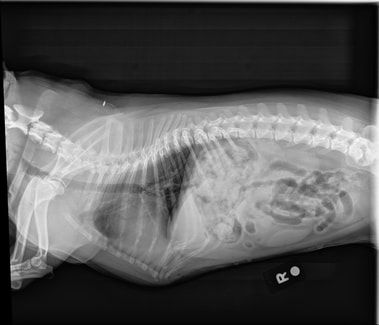

In-House Digital Radiography

South Paw Animal Hospital offers digital radiography at our hospital. Our Sound SmartDR digital imaging unit allows us to take clear and very detailed X-rays. For our patients, this is a much faster procedure as fewer images need to be taken. For our customers, we can share images digitally with them as well as referral specialty hospitals.

Radiographs can help evaluate health issues such as fractures, arthritis, cardiac abnormalities, or foreign body ingestion. Call (609) 465-9006 to schedule an appointment.